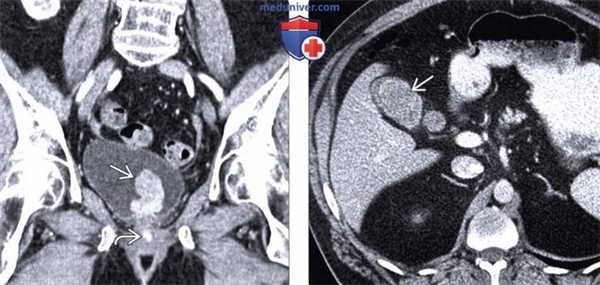

(Слева) На КТ с контрастным усилением в корональной плоскости определяется усиливающееся при контрастировании объемное образование в мочевом пузыре. Обратите внимание также на гиперденсную зону в уретре, накопившую контраст. Все эти изменения являются проявлениями метастатической меланомы. Поражение мочевого пузыря неотличимо от первичной опухоли без анамнеза заболевания.

(Справа) При аксиальной КТ с контрастным усилением выявлено накапливающее контраст объемное образование в желчном пузыре. В анамнезе - меланома, и это поражение медленно увеличивается в размерах с течением времени. Меланома - самая частая причина метастазов в желчном пузыре.